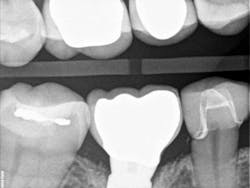

Recently, I changed my protocol for doing Class II dental restorations. I have started using indirect restorations more often. Depending on the size of the restoration, I now use indirect composites, inlays, onlays, and occasionally full-coverage crowns. Using indirect restorations allows one to control the emergence profile of the restoration and also ensures tight proximal and broad interproximal contacts. See Figures 3 through 6.

embrasure space. Distal of No. 28 was restored as well;

not seen in this radiograph.